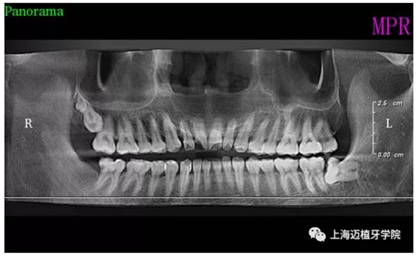

主訴:前門(mén)外傷牙根折要求修復(fù)?現(xiàn)病史:前門(mén)牙外傷,劈裂至根部,無(wú)法固定及其他修復(fù),要求種植?檢查:11牙冠2/3缺損,唇腭向劈裂,唇部紅腫。 CT示根折, 骨寬度9.47mm,距鼻底12.34mm,Ⅲ類骨。 口腔衛(wèi)生一般

術(shù)前全景片

術(shù)后全景片